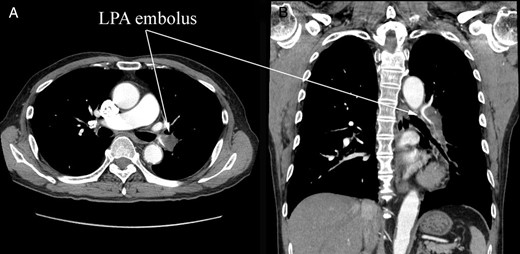

A 74-year-old male patient was referred to our hospital for the treatment of a right atrial tumor. He had experienced the sudden onset of dyspnea and had gone to another hospital. There, transthoracic echocardiography revealed the right atrial tumor. After his transfer to our hospital, transthoracic echocardiography was performed again. The right atrial tumor, which adhered to the interatrial septum, had a tail-like surface projection. The tumor projection was mobile and prolapsed into the right ventricle during diastole (Fig. 1). In addition, the right cardiac cavities were dilated and the estimated right ventricle pressure was 63 mmHg, which suggested the presence of moderate pulmonary hypertension. Subsequently, computed tomography (CT) showed that the left pulmonary artery was occluded by a large embolus (Fig. 2). Because the embolus formed acute angles with the vessel wall, acute pulmonary embolism was highly suspected. We performed an emergency surgery for the removal of both the right atrial tumor and the embolus in the left pulmonary artery.

Preoperative CT. (A) Cross section and (B) coronary section. A large embolus stuck into the left pulmonary artery (LPA). The embolus formed acute angles with the vessel wall, which suggested an acute pulmonary embolism.